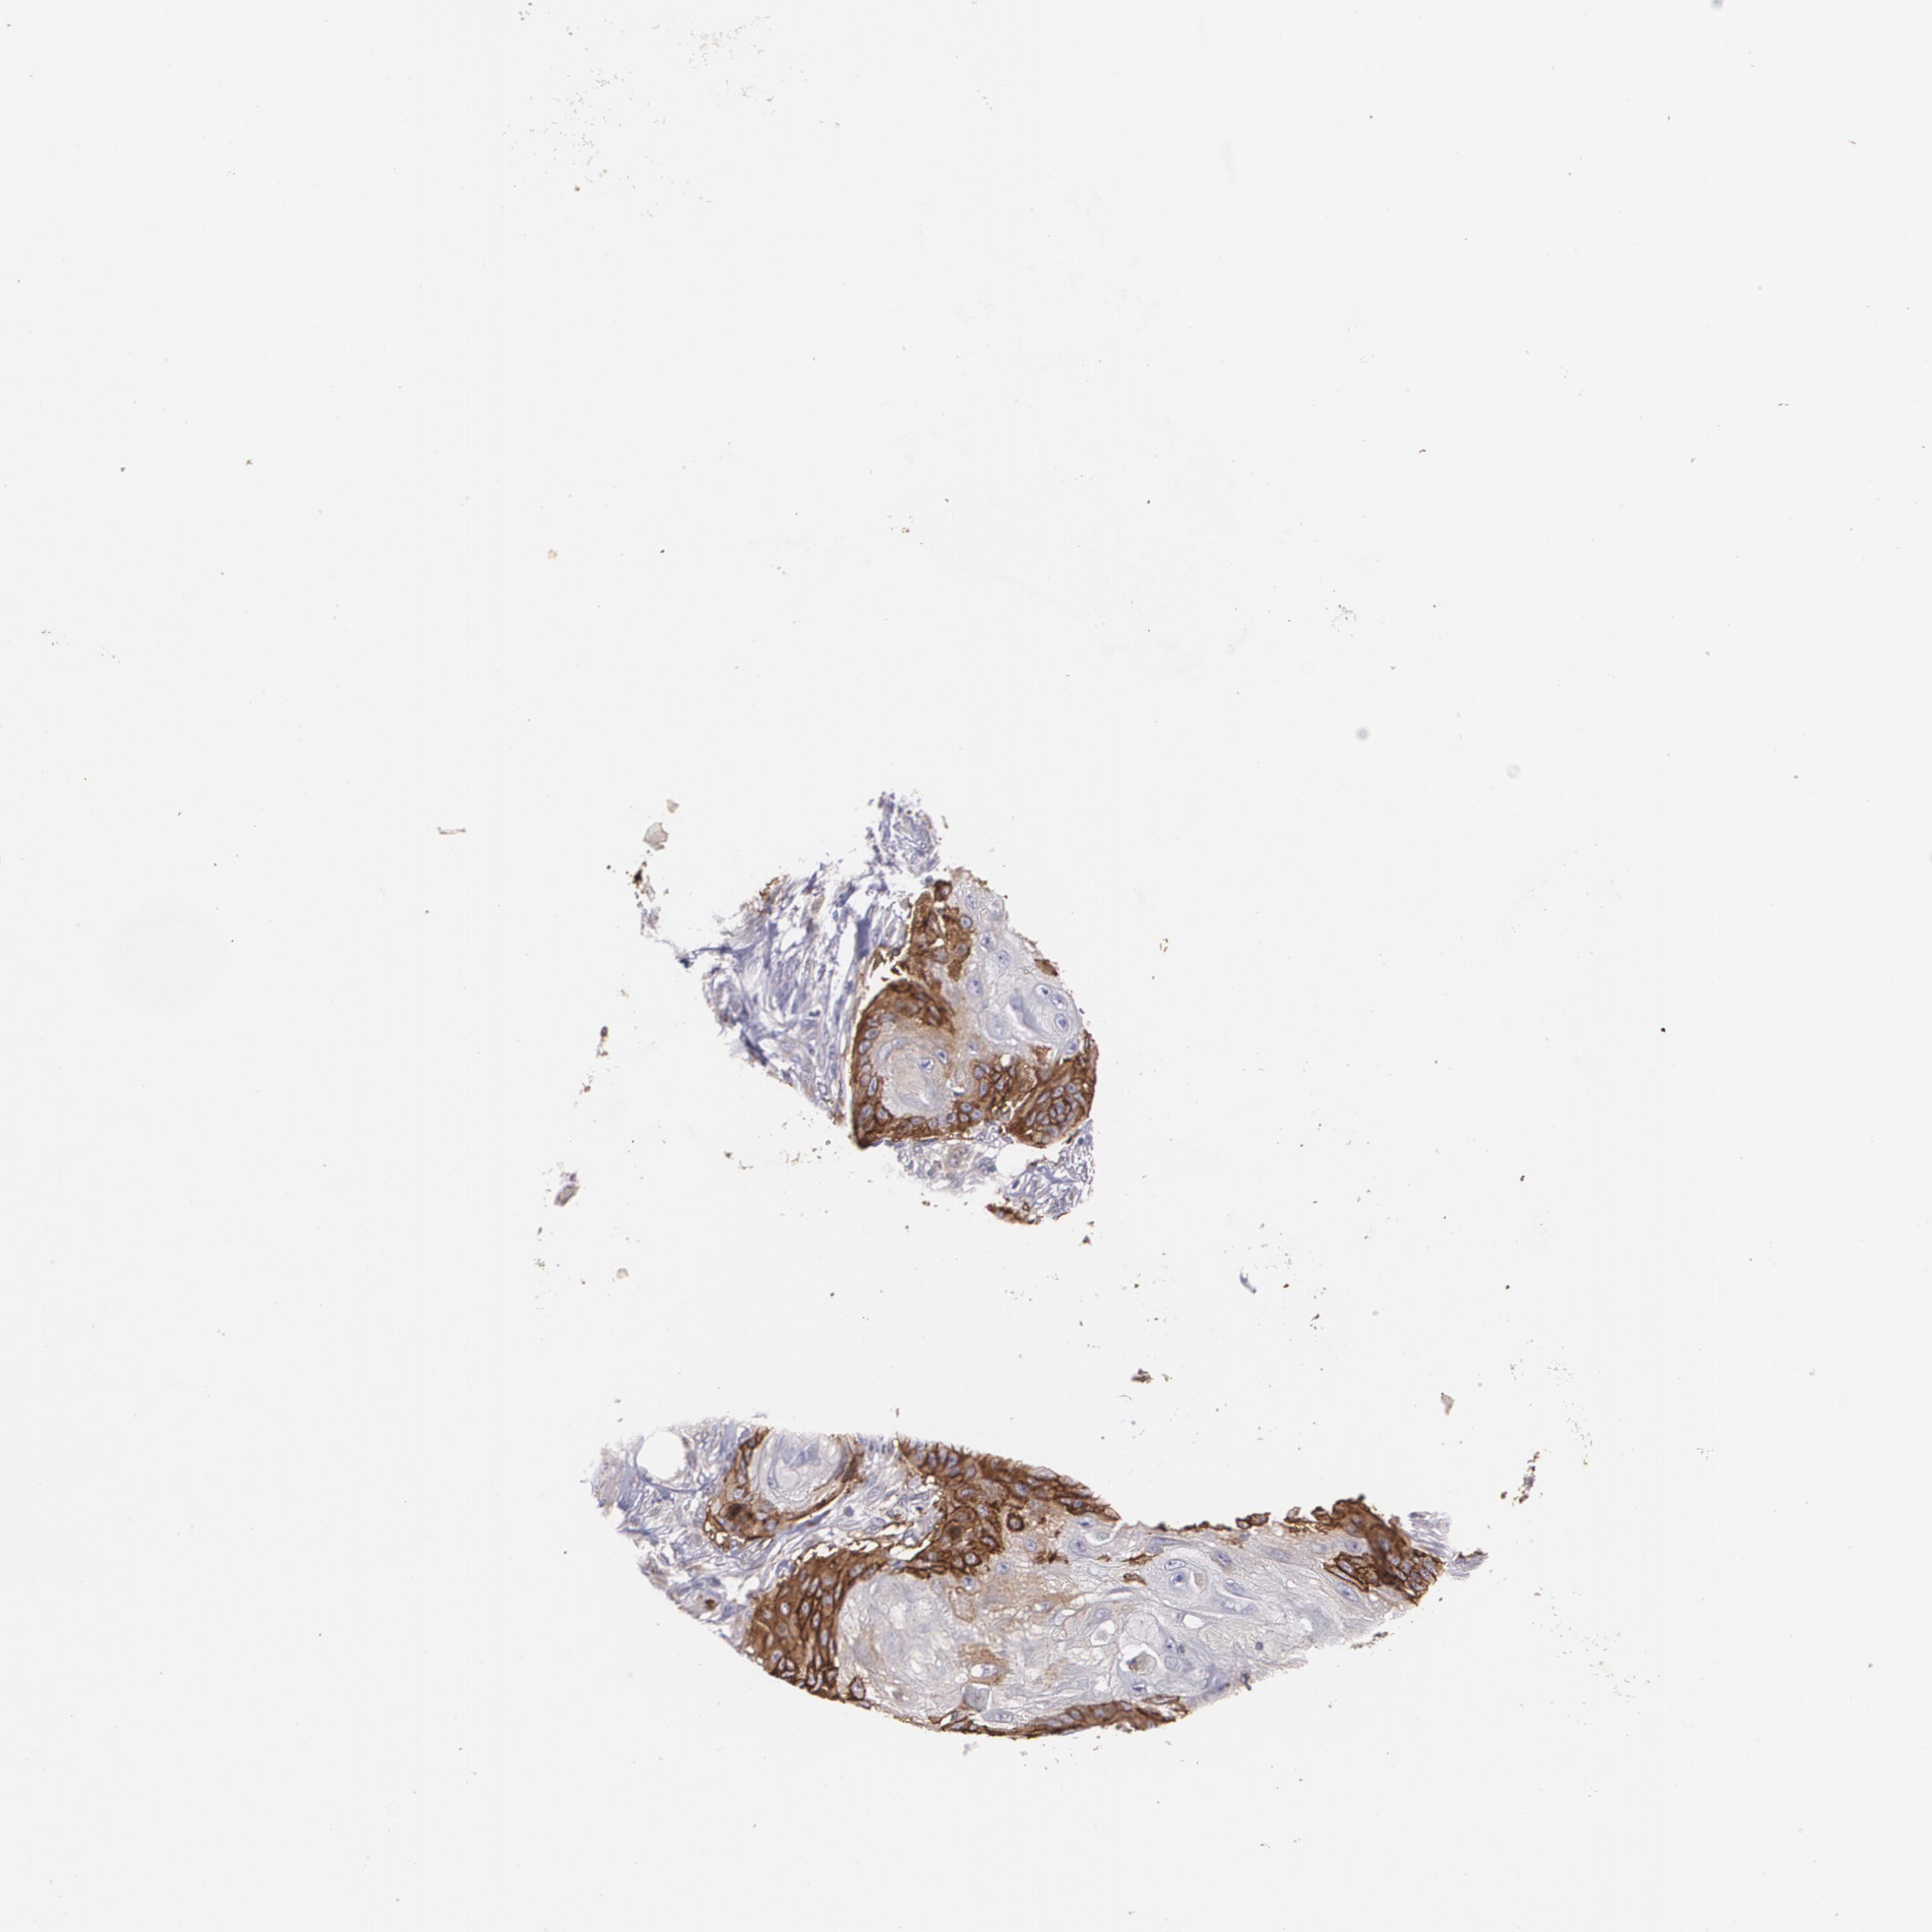

Basal cell and squamous cell cancer

SKIN CANCER - Protein expressioni

A mouse-over function shows sample information and annotation data. Click on an image to view it in a full screen mode. Samples can be filtered based on level of antibody staining by selecting one or several of the following categories: high, medium, low and not detected. The assay and annotation is described here.

Each image is clickable and will lead to virtual microscopy that enables deeper exploration of all samples and also displays staining intensity scores, fraction scores and subcellular localization as well as patient and tissue information for each sample.

Antibody CAB002759

Squamous cell carcinoma, metastatic, NOS